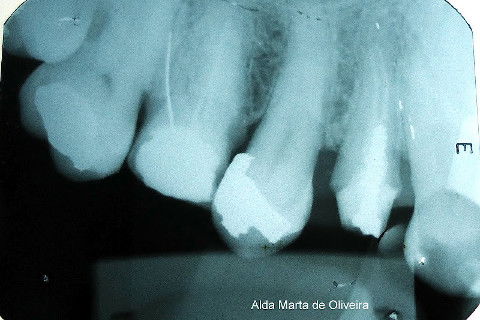

Paciente de 52 anos, gênero masculino, leucoderma.

QP: dente 14 era portador de um "pivot" que "vivia se soltando e agora não parava mais..."

- Radiografia de diagnóstico;

- Preparo do conduto, instalação de pino rosqueável e confecção de NP em resina;